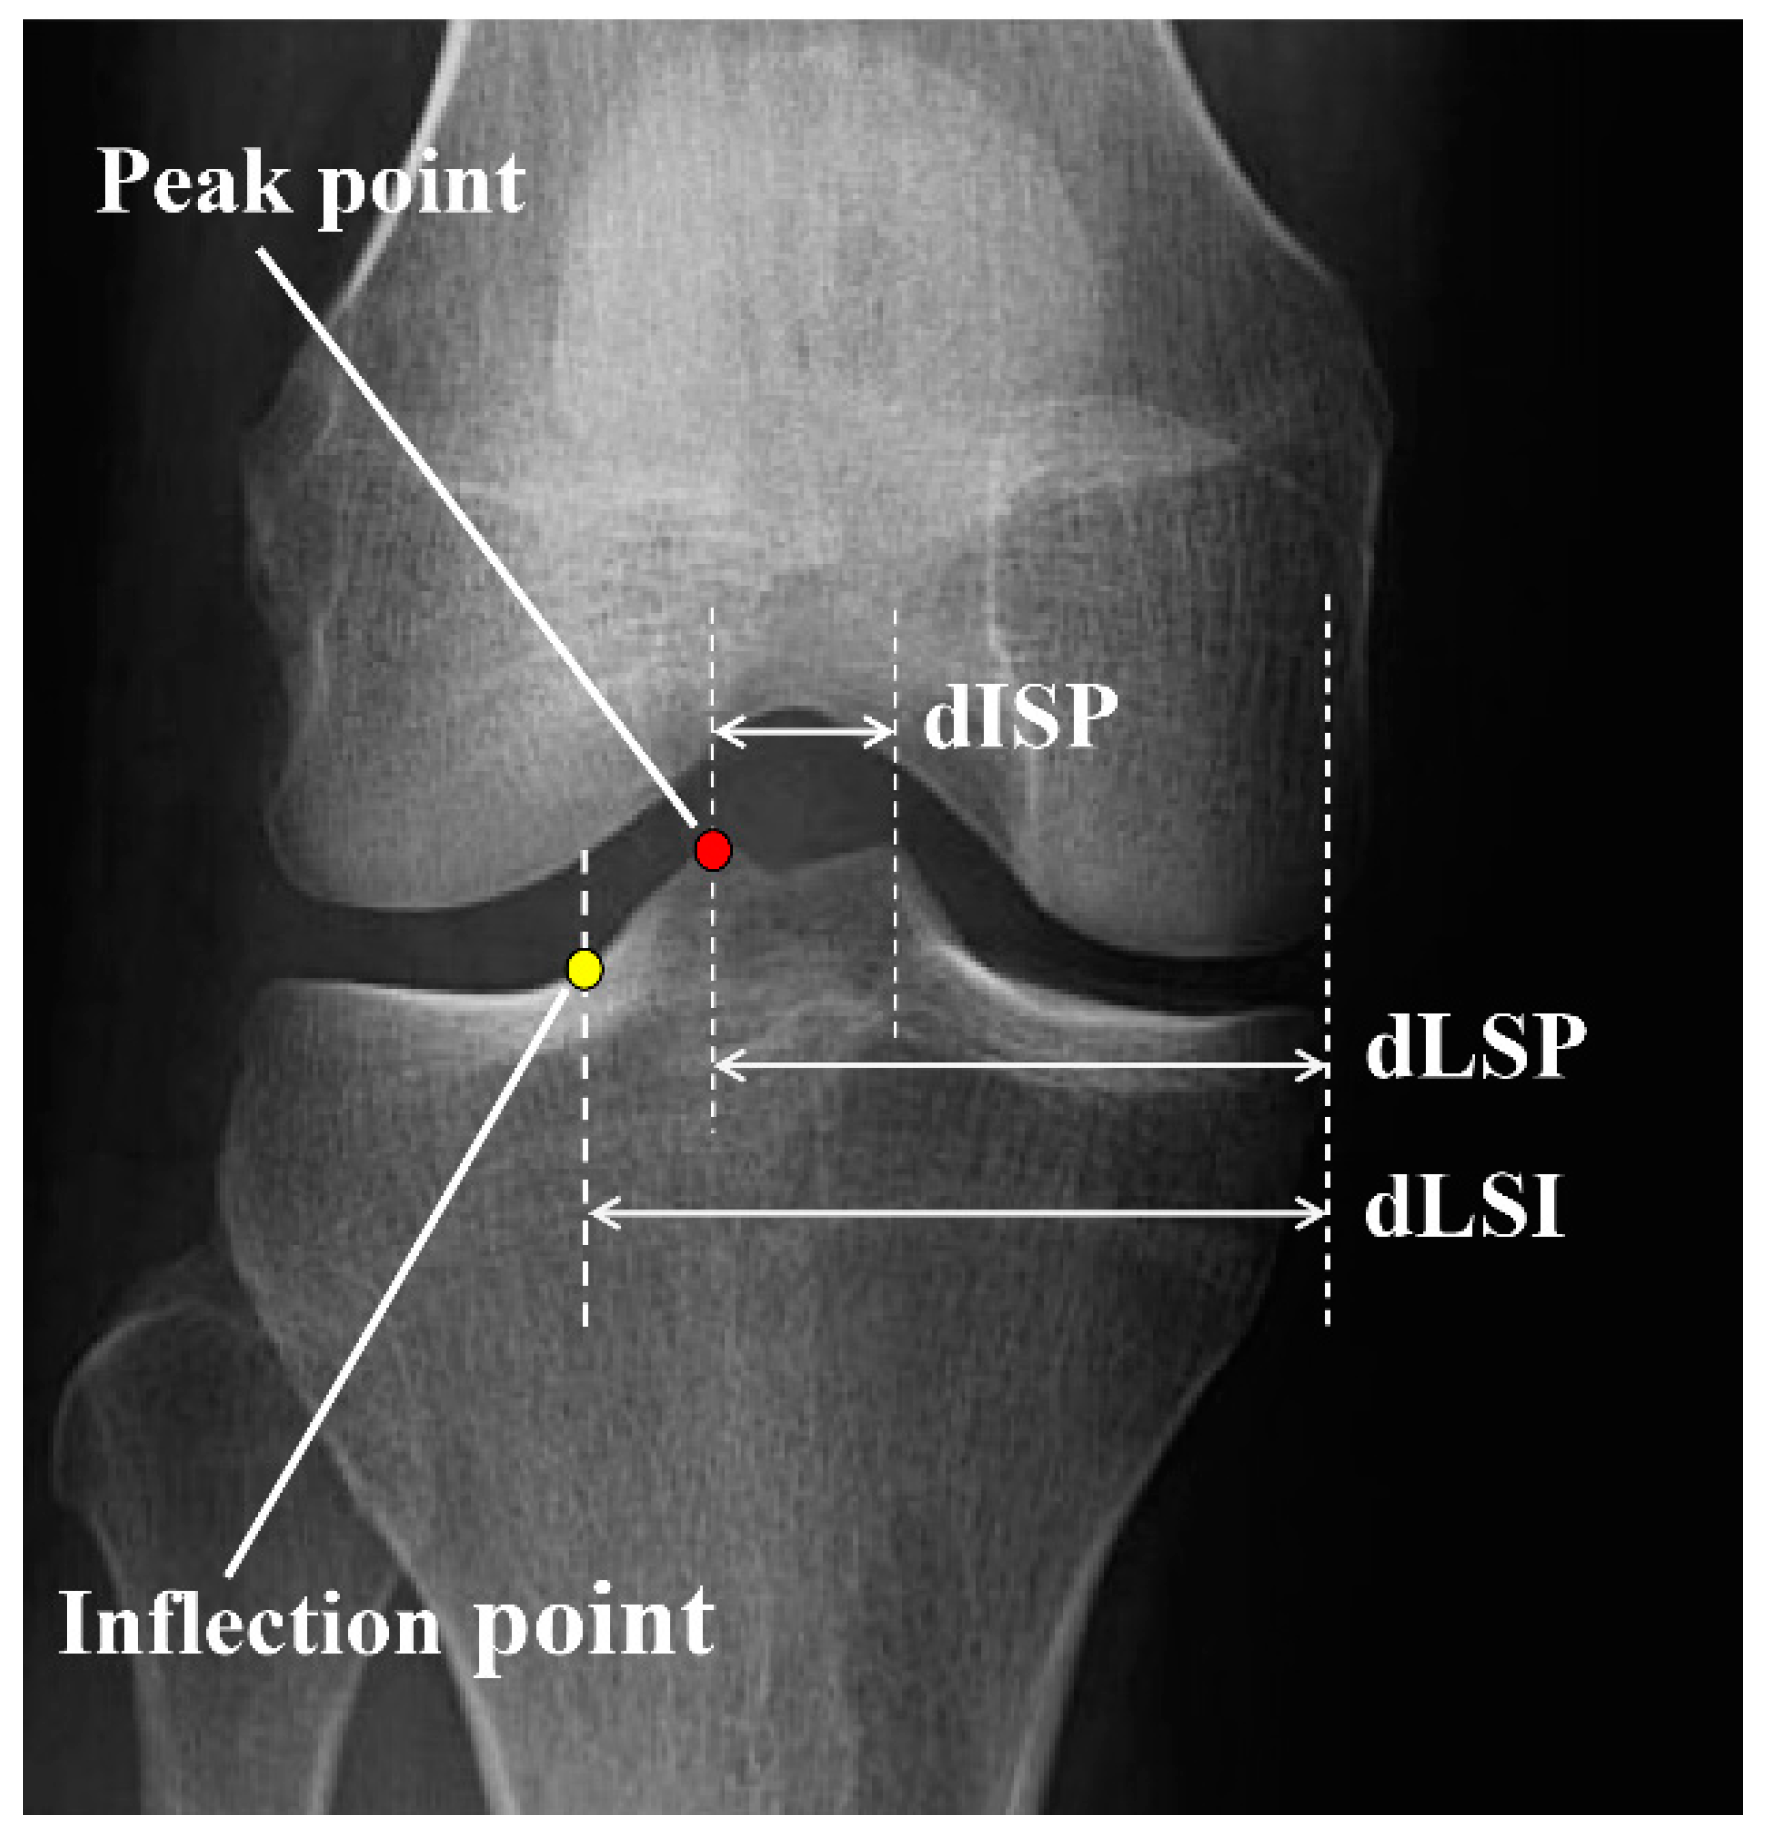

The peak and inflection points of the lateral tibial spine were determined as the most prominent points and the intersection point between the tibial spine slope and the tibial plateau, respectively. The distance between the medial tibial border and lateral spine peak point (dLSP), the distance between the medial tibial border and lateral spine inflection point (dLSI), and the mediolateral inter-spine distance (dISP) were measured and presented as a percentage of the entire tibial plateau width (Figure 1).

Figure 1.

Radiographic measurements of the lateral tibial spine. Peak point: the most prominent point of the lateral tibial spine, inflection point: the intersection point between the tibial spine slope and tibial plateau, dLSP: distance between the tibial medial border and lateral spine peak point, dLSI: distance between the tibial medial border and lateral spine inflection point; dISP: medio-lateral inter-spine distance.